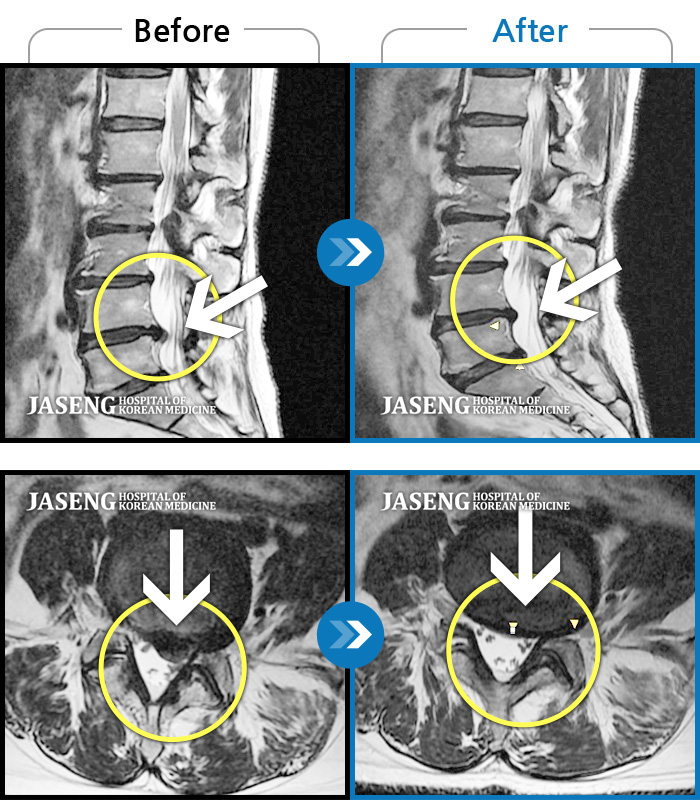

허리디스크

해운대 · 이상건 원장

허리 골반통증 및 우 하지 방산통

촬영시기

2017.05.29 ~ 2017.12.27

2017.12.28

조회수 2,200